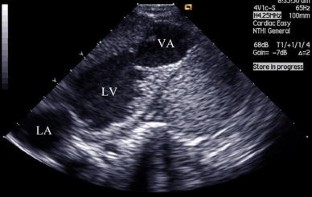

Fig. 1